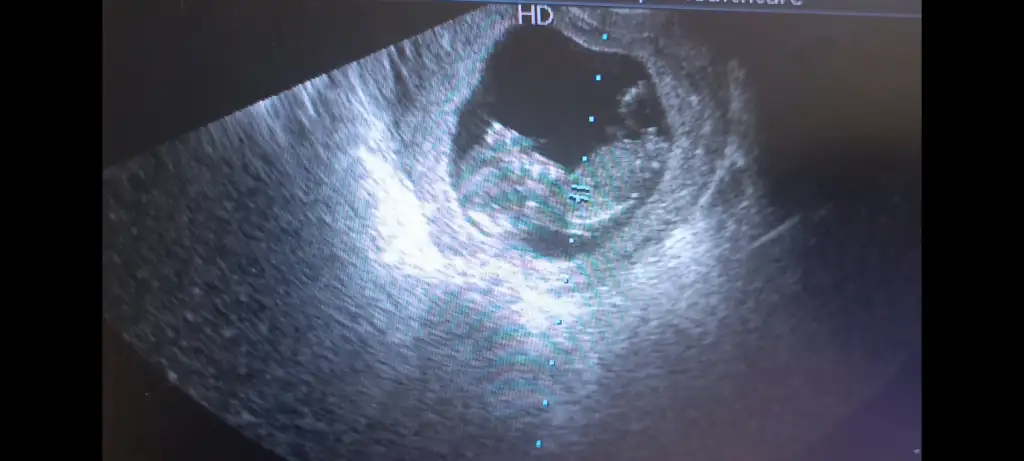

Benimde 7 aydır sağ tarafim da batma vardı. Her ay hissediyordum. Gebelikte te de ara ara hissetmeye devam ettim. Muhtemelen büyük bir kistim vardı. Doktorlar bir şey demedi ama sürekli aynı yerde hissettiğim için diyorum. Geçen gün çocuklarla uğraşırken biraz zorlandım. O sıra o batan yer biraz daha ağrıdı. Peşinden hafif kahverengi akıntı geldi. O günden beri batma hissi kayboldu. Sanırım o gün kistim patladı. Allahu alem.Hanımlar benim sürekli sol kasigim ağrıyor batma şeklinde gebeliğin başından beri ağrısı bazen sol bacağıma vuruyor sizde de tek taraflı kasik ağrıları oluyor mu . Bende ayrıca çikolata kistim var ondan mi kaynaklı yoksa gebeliğin belirtilerinden mi bu .